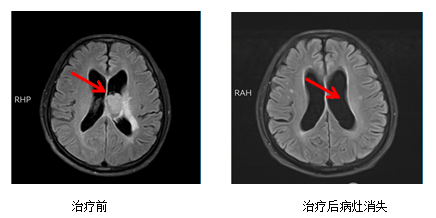

病例一:颅内单发转移瘤

治疗前治疗后病灶消失